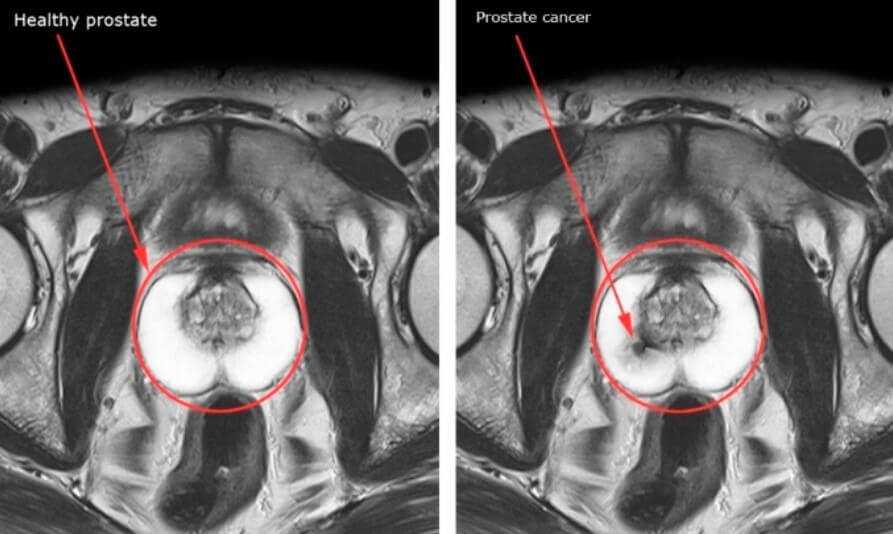

При необходимости проводят МРТ предстательной железы

На фото ниже показано раннее выявление рака простаты при помощи МРТ.